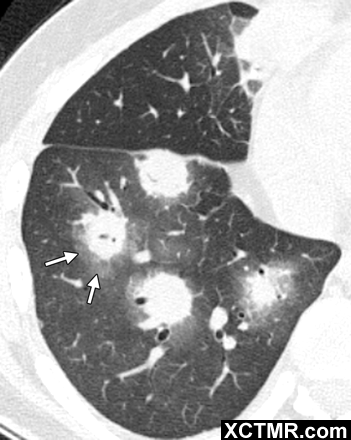

p>晕征是指某些疾病的肺ct 表现 晕征是一种磨玻璃影围绕结节或肿块